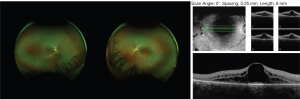

Case 1 is a now 20-year-old Hispanic female who presented with decreased central vision at around age 13 years and well controlled generalized tonic clonic seizures (GTC) since age 7 years of age as reported by Sanchez et al. (10). She has a diagnosis of CLN8 based on a likely pathogenic deletion encompassing the entire CLN8 gene and a c.200C>T (p.A67V) variant of unknown significance on this gene confirmed in trans, and electron microscopy of lymphocytes showing intracytoplasmic inclusions. She was noted to have cystoid macular edema (CME) bilaterally, with visual acuity of 20/40 OU at time of initial report and more recently OD 20/80 +2 and OS 20/100. On follow up ophthalmologic evaluation she had attenuated vasculature with cystoid macular edema and diffuse retinal pigment epithelium mottling (Figure 6) as well as trace posterior subcapsular cataract (PSC). Spectral domain OCT had demonstrated macular cystic change and diffuse macular schisis involving the outer nuclear and the outer plexiform layers. In the past year, OCT showed the retinal CME persists but has had mild improvement. Goldmann visual field (GVF) revealed large central scotomas bilaterally which have been stable on follow up. She has had one breakthrough seizure described as GTC after original report that lasted 5 minutes and post-ictal state of 10 minutes with sleepiness. She has been well controlled with Keppra since this episode. No repeat brain imaging has been done. Following the original report, she had formal psychological evaluation showing anxiety and depression but normal cognitive function.

Descriptions of the ophthalmic findings from routine ophthalmologic examination are provided for the sibling pair of CLN8 patients. Retinal imaging was acquired, including ultrawide field color fundus imaging (Optos, United Kingdom) and spectral domain OCT (Zeiss Cirrus instrument, Germany).